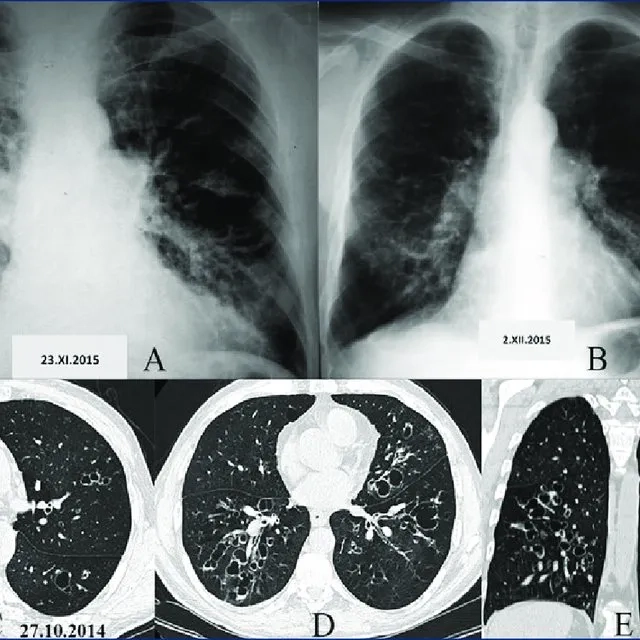

Diagram of lungs with Bronchiectasis